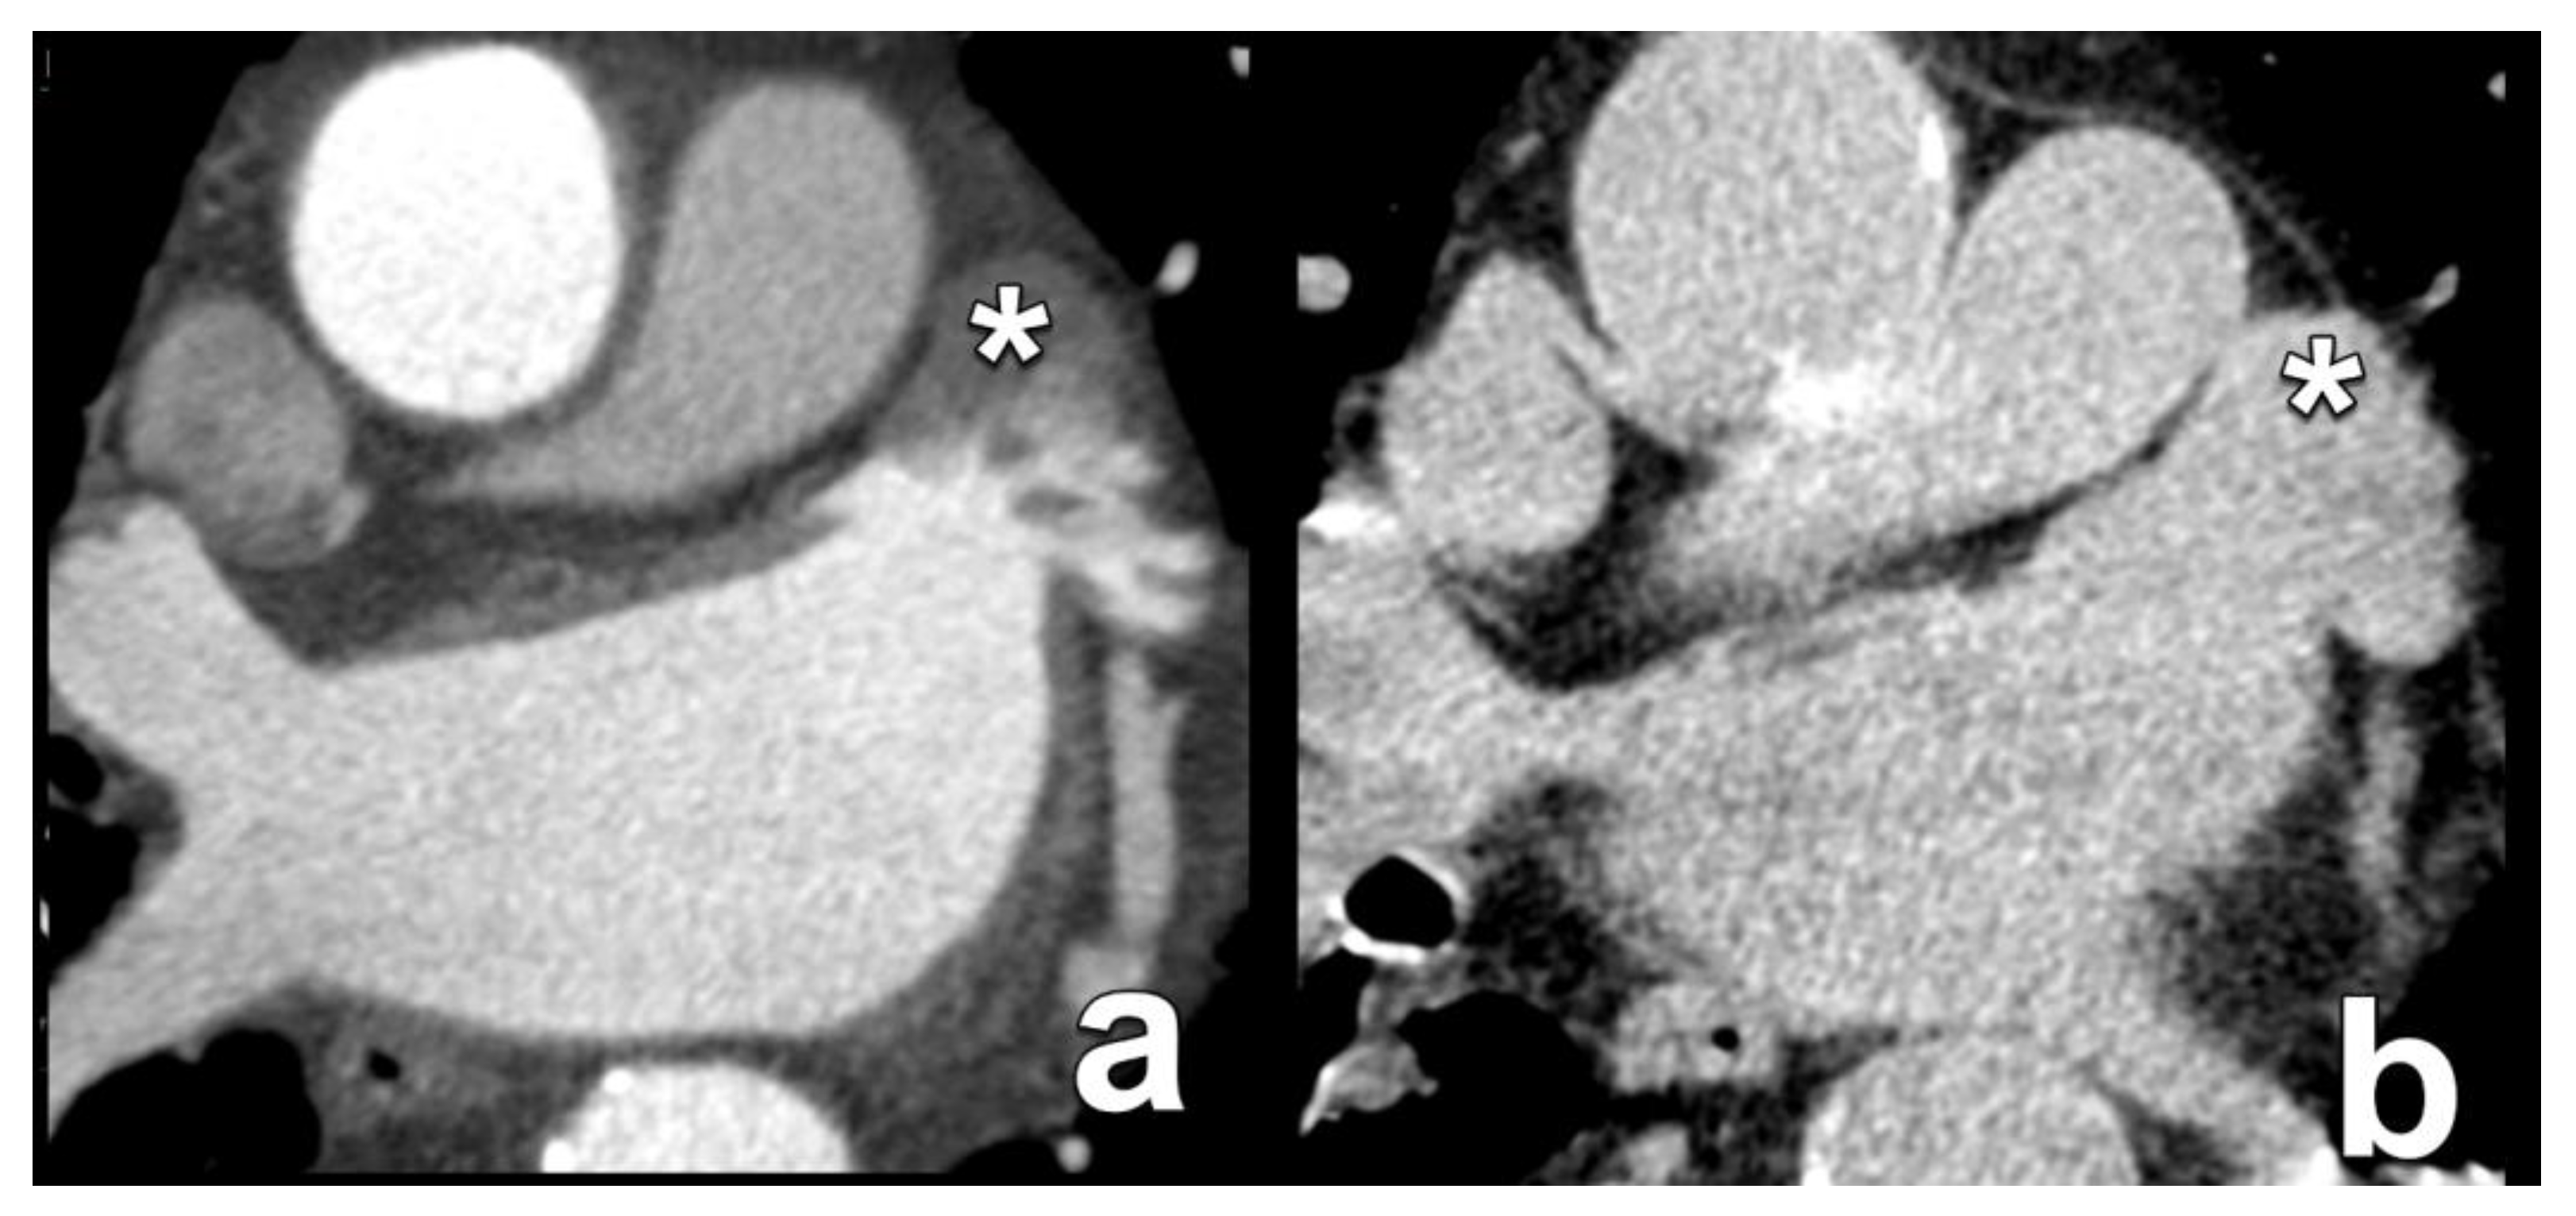

- Korsholm, K.; Berti, S.; Iriart, X.; Saw, J.; Wang, D.D.; Cochet, H.; Chow, D.; Clemente, A.; De Backer, O.; Jensen, J.M.; et al. Expert Recommendations on Cardiac Computed Tomography for Planning Transcatheter Left Atrial Appendage Occlusion. JACC Cardiovasc. Interv. 2020, 13, 277–292. [Google Scholar] [CrossRef] [PubMed]

- Rajwani, A.; Nelson, A.J.; Shirazi, M.G.; Disney, P.J.; Teo, K.S.; Wong, D.T.; Young, G.D.; Worthley, S.G. CT sizing for left atrial appendage closure is associated with favourable outcomes for procedural safety. Eur. Heart J. Cardiovasc. Imaging 2017, 18, 1361–1368. [Google Scholar] [CrossRef]

- Chun, S.H.; Suh, Y.J.; Han, K.; Park, S.J.; Shim, C.Y.; Hong, G.-R.; Lee, S.; Lee, S.-H.; Kim, Y.J.; Choi, B.W. Differentiation of left atrial appendage thrombus from circulatory stasis using cardiac CT radiomics in patients with valvular heart disease. Eur. Radiol. 2021, 31, 1130–1139. [Google Scholar] [CrossRef] [PubMed]

- Teunissen, C.; Habets, J.; Velthuis, B.K.; Cramer, M.J.; Loh, P. Double-contrast, single-phase computed tomography angiography for ruling out left atrial appendage thrombus prior to atrial fibrillation ablation. Int. J. Cardiovasc. Imaging 2017, 33, 121–128. [Google Scholar] [CrossRef] [PubMed]